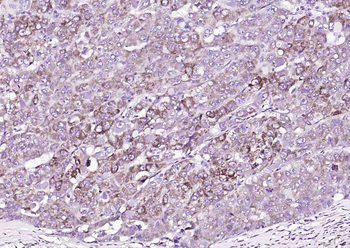

Fixative-fixed, paraffin embedded (human liver carcinoma), Antigen retrieval by boiling in sodium citrate buffer (pH6.0) for 15 min, Block endogenous peroxidase by 3% hydrogen peroxide for 20 minutes, Blocking buffer (normal goat serum) at 37°C for 30 min, Antibody incubation with (SGPL1) Polyclonal Antibody, Unconjugated (orb4560) at 1:200 overnight at 4°C, followed by operating according to SP Kit (Rabbit) instructionsand DAB staining.